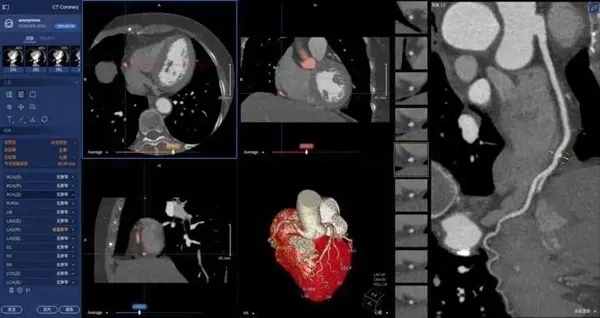

02、在醫(yī)學(xué)上的應(yīng)用

在醫(yī)學(xué)領(lǐng)域,機(jī)器視覺(jué)主要用于醫(yī)學(xué)輔助診斷。首先采集核磁共振、超聲波、激光、X射線、γ射線等對(duì)人體檢查記錄的圖像,再利用數(shù)字圖像處理技術(shù)、信息融合技術(shù)對(duì)這些醫(yī)學(xué)圖像進(jìn)行分析、描述和識(shí)別,最后得出相關(guān)信息,對(duì)輔助醫(yī)生診斷人體病源大小、形狀和異常,并進(jìn)行有效治療發(fā)揮了重要的作用。不同醫(yī)學(xué)影像設(shè)備得到的是不同特性的生物組織圖像,如X射線反映的是骨骼組織,核磁共振影像反映的是有機(jī)組織圖像,而醫(yī)生往往需要考慮骨骼有機(jī)組織的關(guān)系,因而需要利用數(shù)字圖像處理技術(shù)將兩種圖像適當(dāng)?shù)丿B加起來(lái),以便于醫(yī)學(xué)分析。